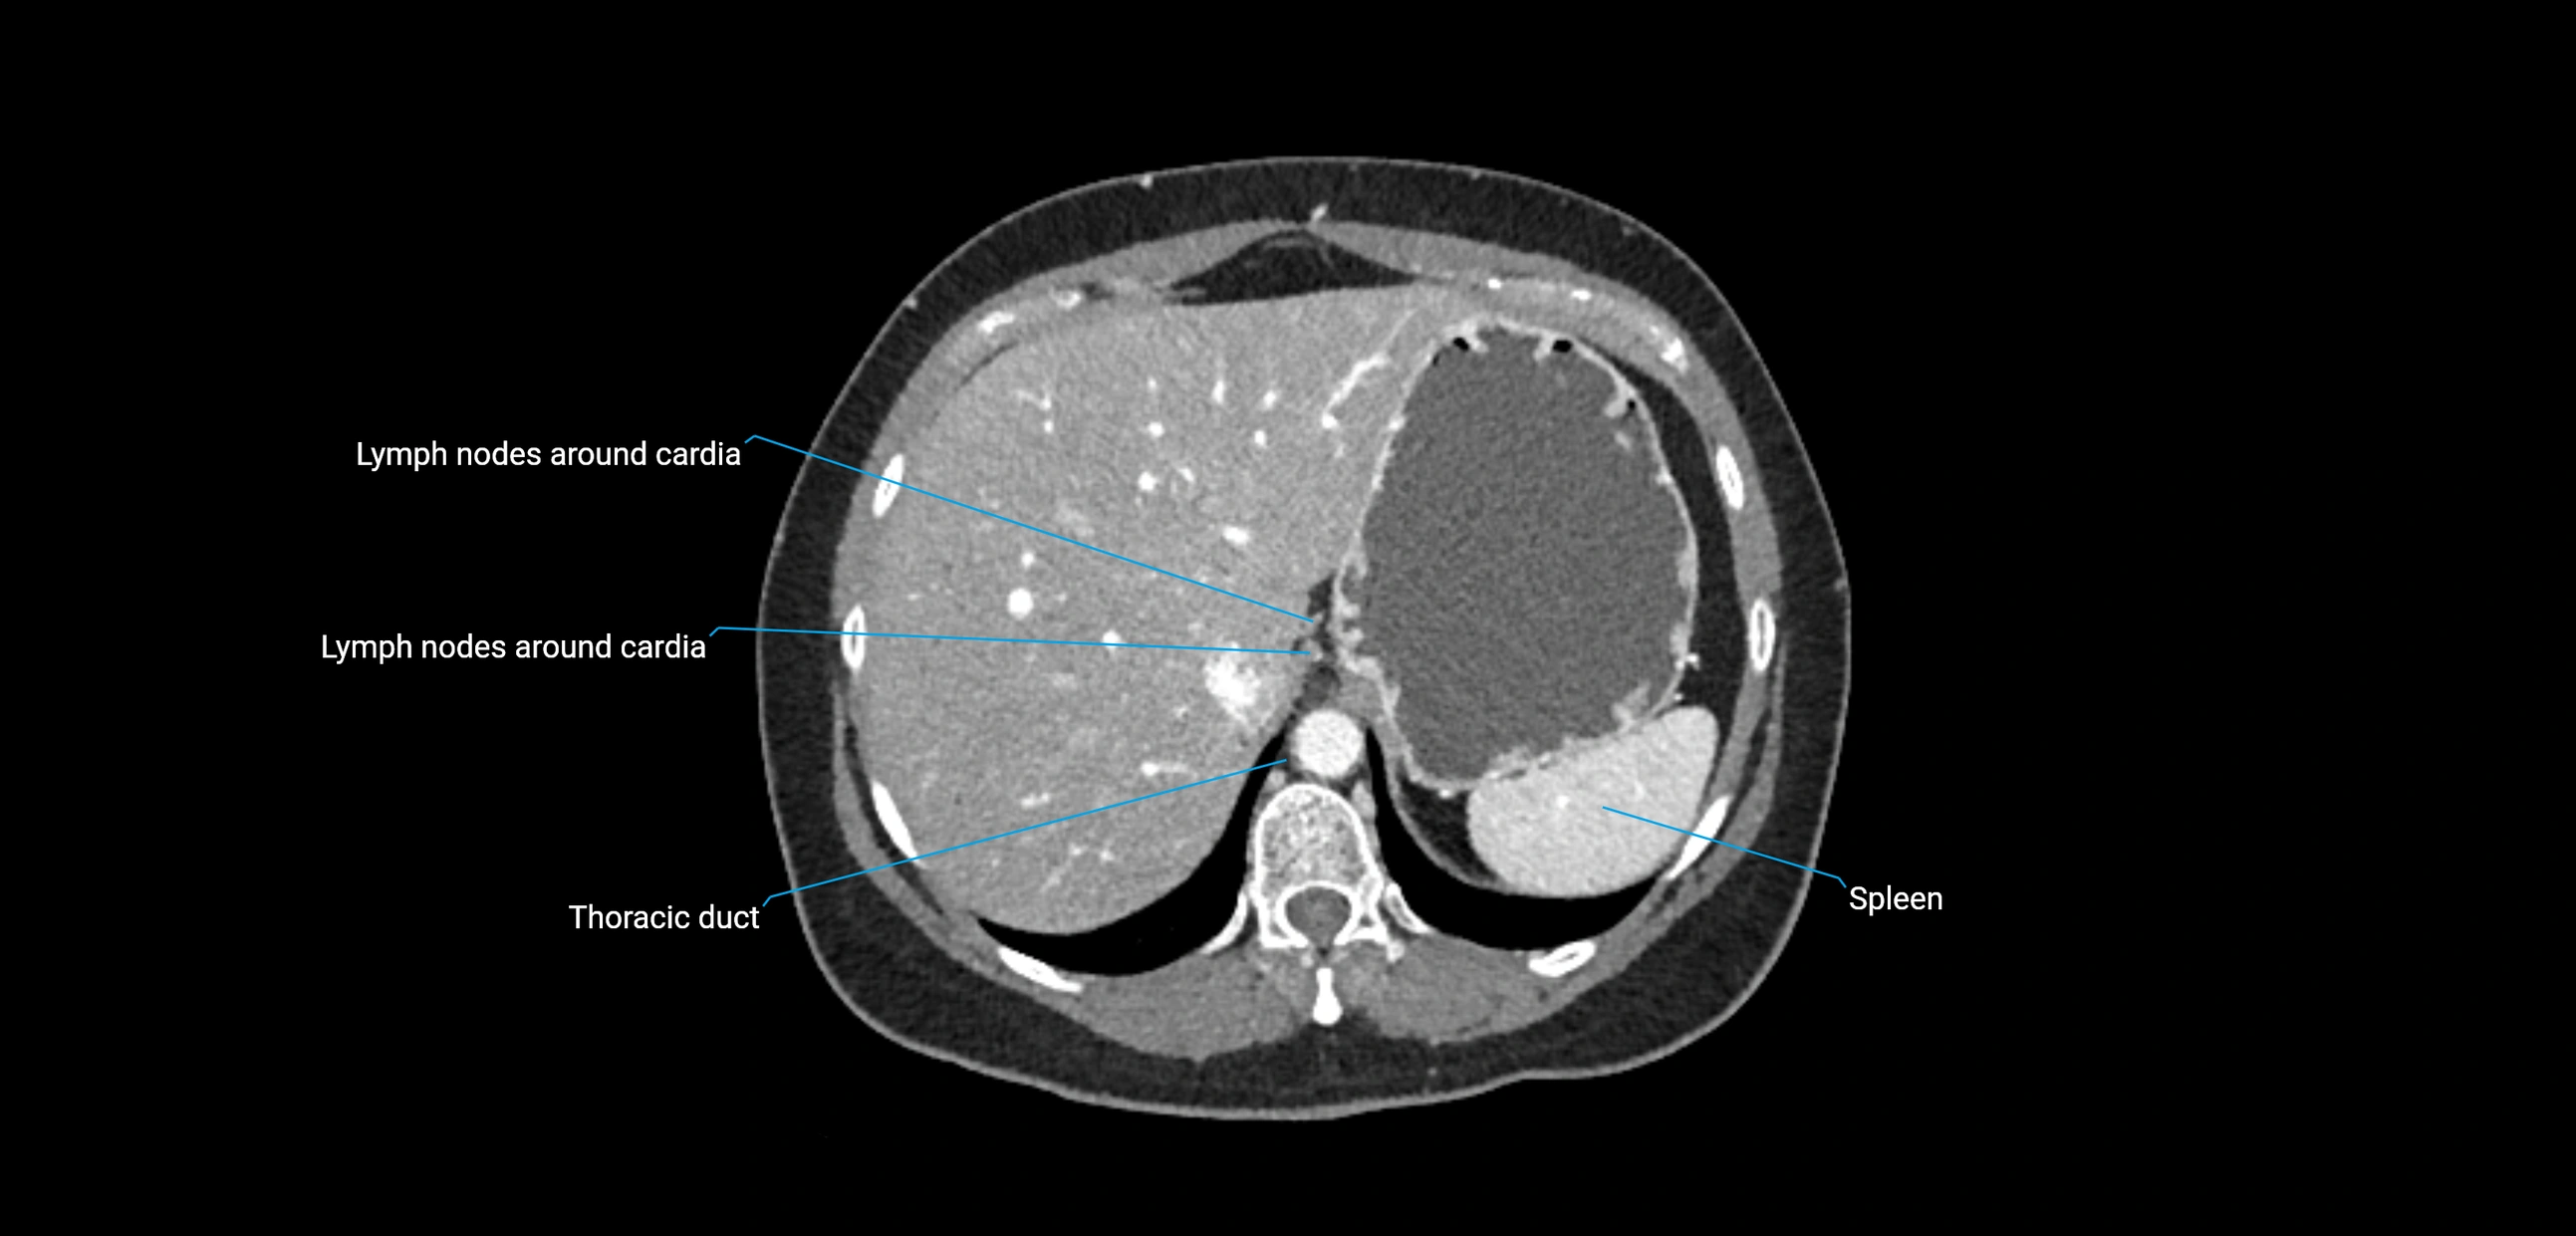

CT Appearance

CT Pre-Contrast:

• Nodes appear as soft-tissue density nodules adjacent to the aorta and IVC

• Calcification may be seen in chronic infections (e.g., tuberculosis)

CT Post-Contrast:

• Normal nodes enhance homogeneously

• Malignant nodes may show heterogeneous enhancement, central necrosis, or conglomerate formation

• Size >1 cm short axis is suspicious, though morphology and distribution are equally important